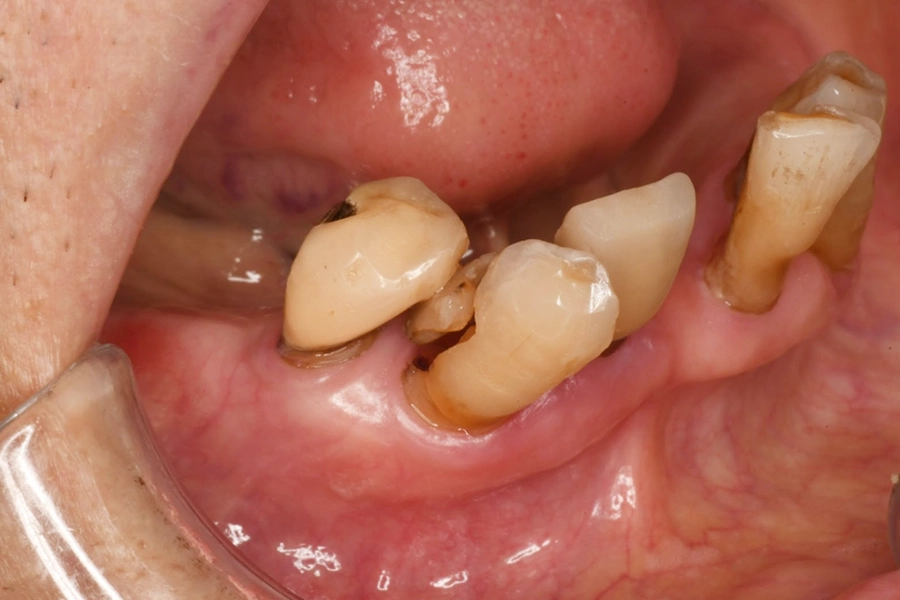

治療中の様子

歯冠部分に限局した歯の破折

破折片の除去